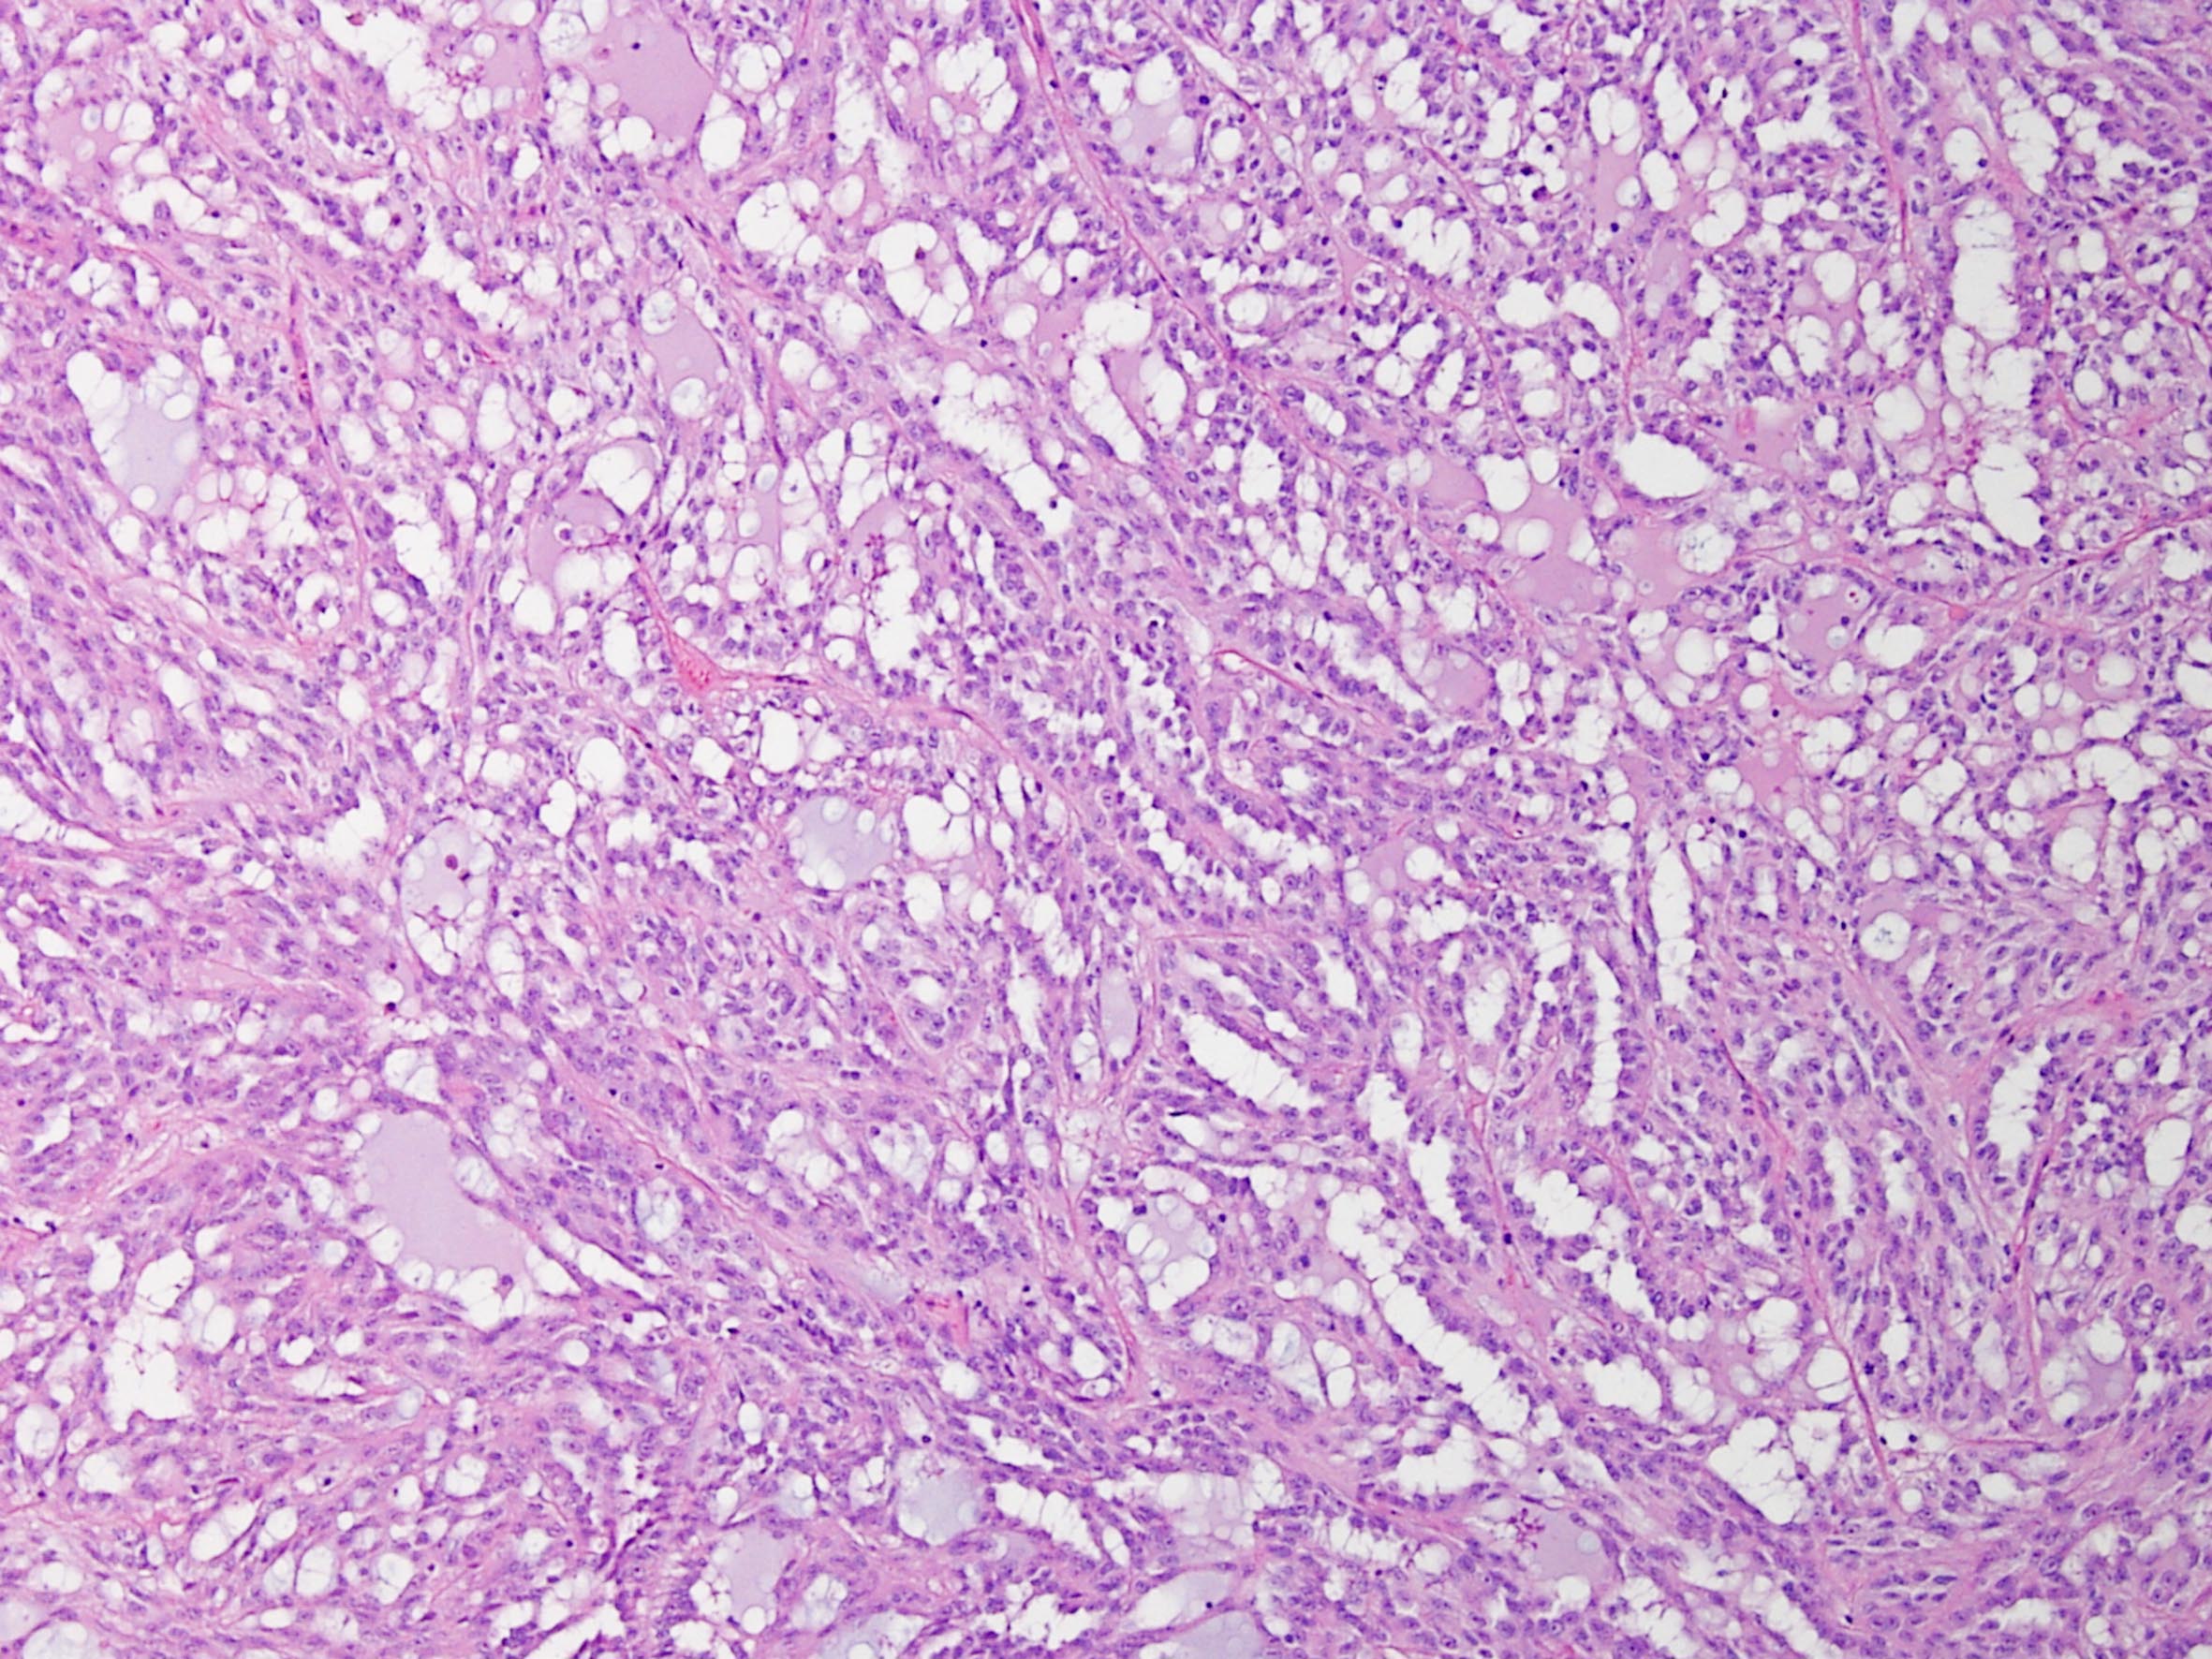

Classification of renal tumors

Case ID: 171